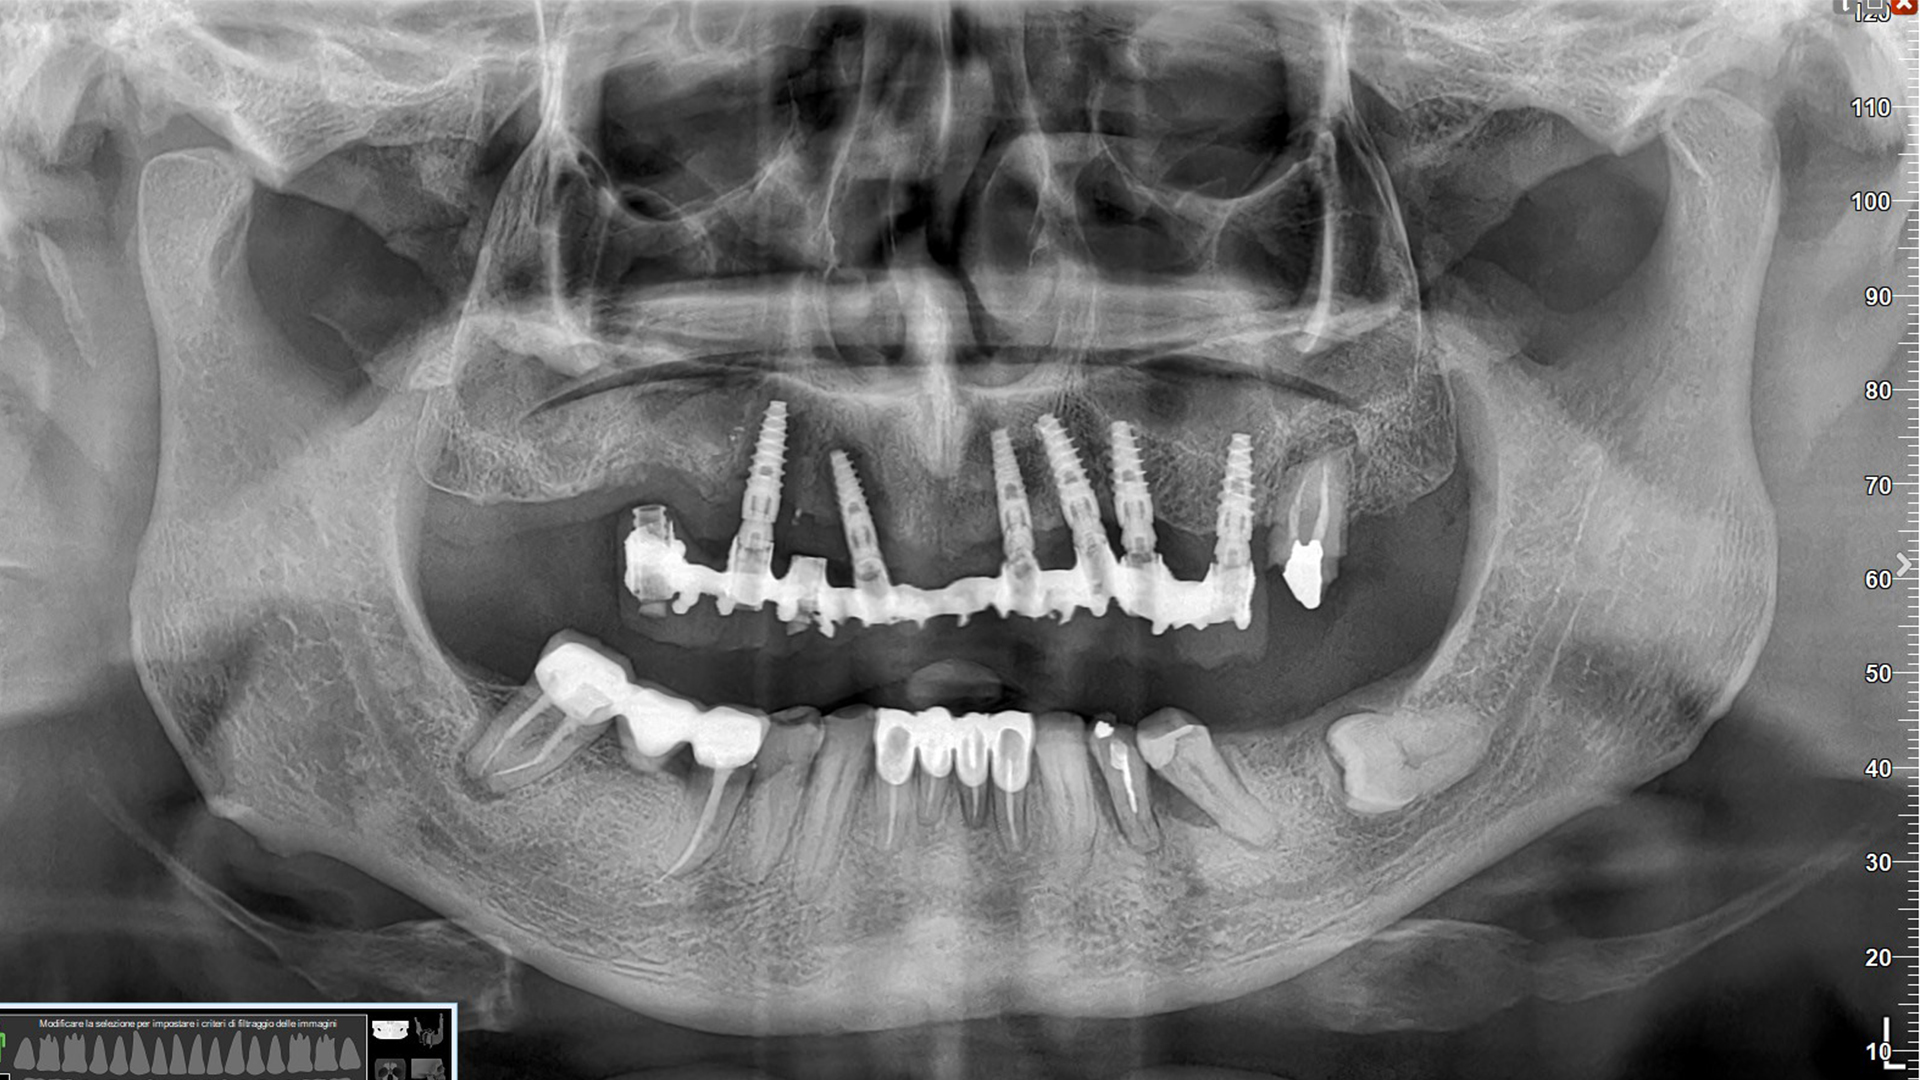

panoramica